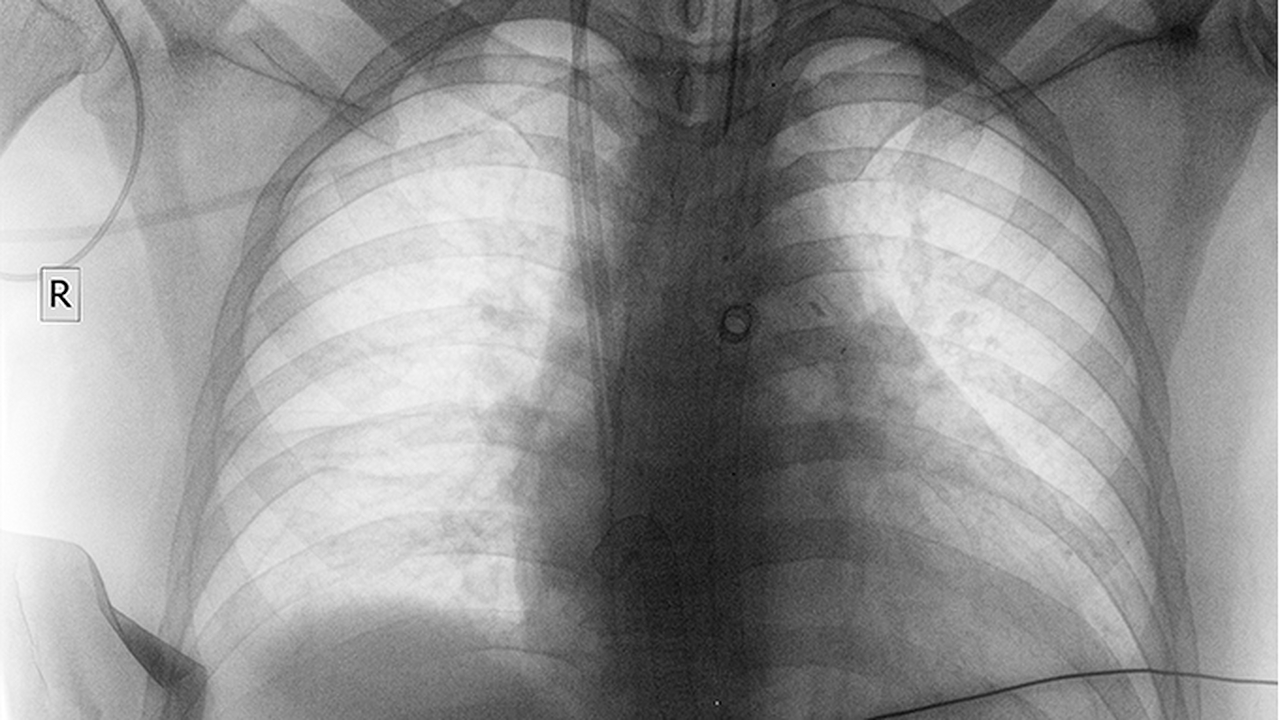

肺癌是全球范围内发病率和死亡率较高的恶性肿瘤之一,其发病原因复杂,包括吸烟、环境污染、职业暴露、遗传因素等。早期诊断和规范治疗对提高患者生存率至关重要。